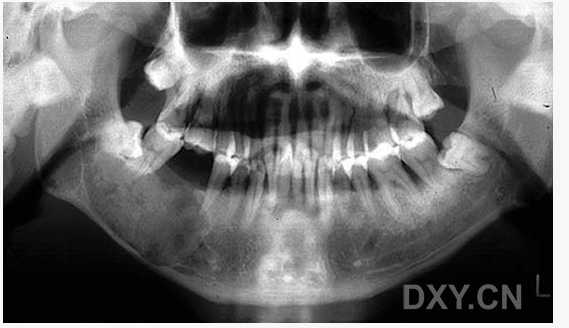

骨髓炎

含牙囊腫